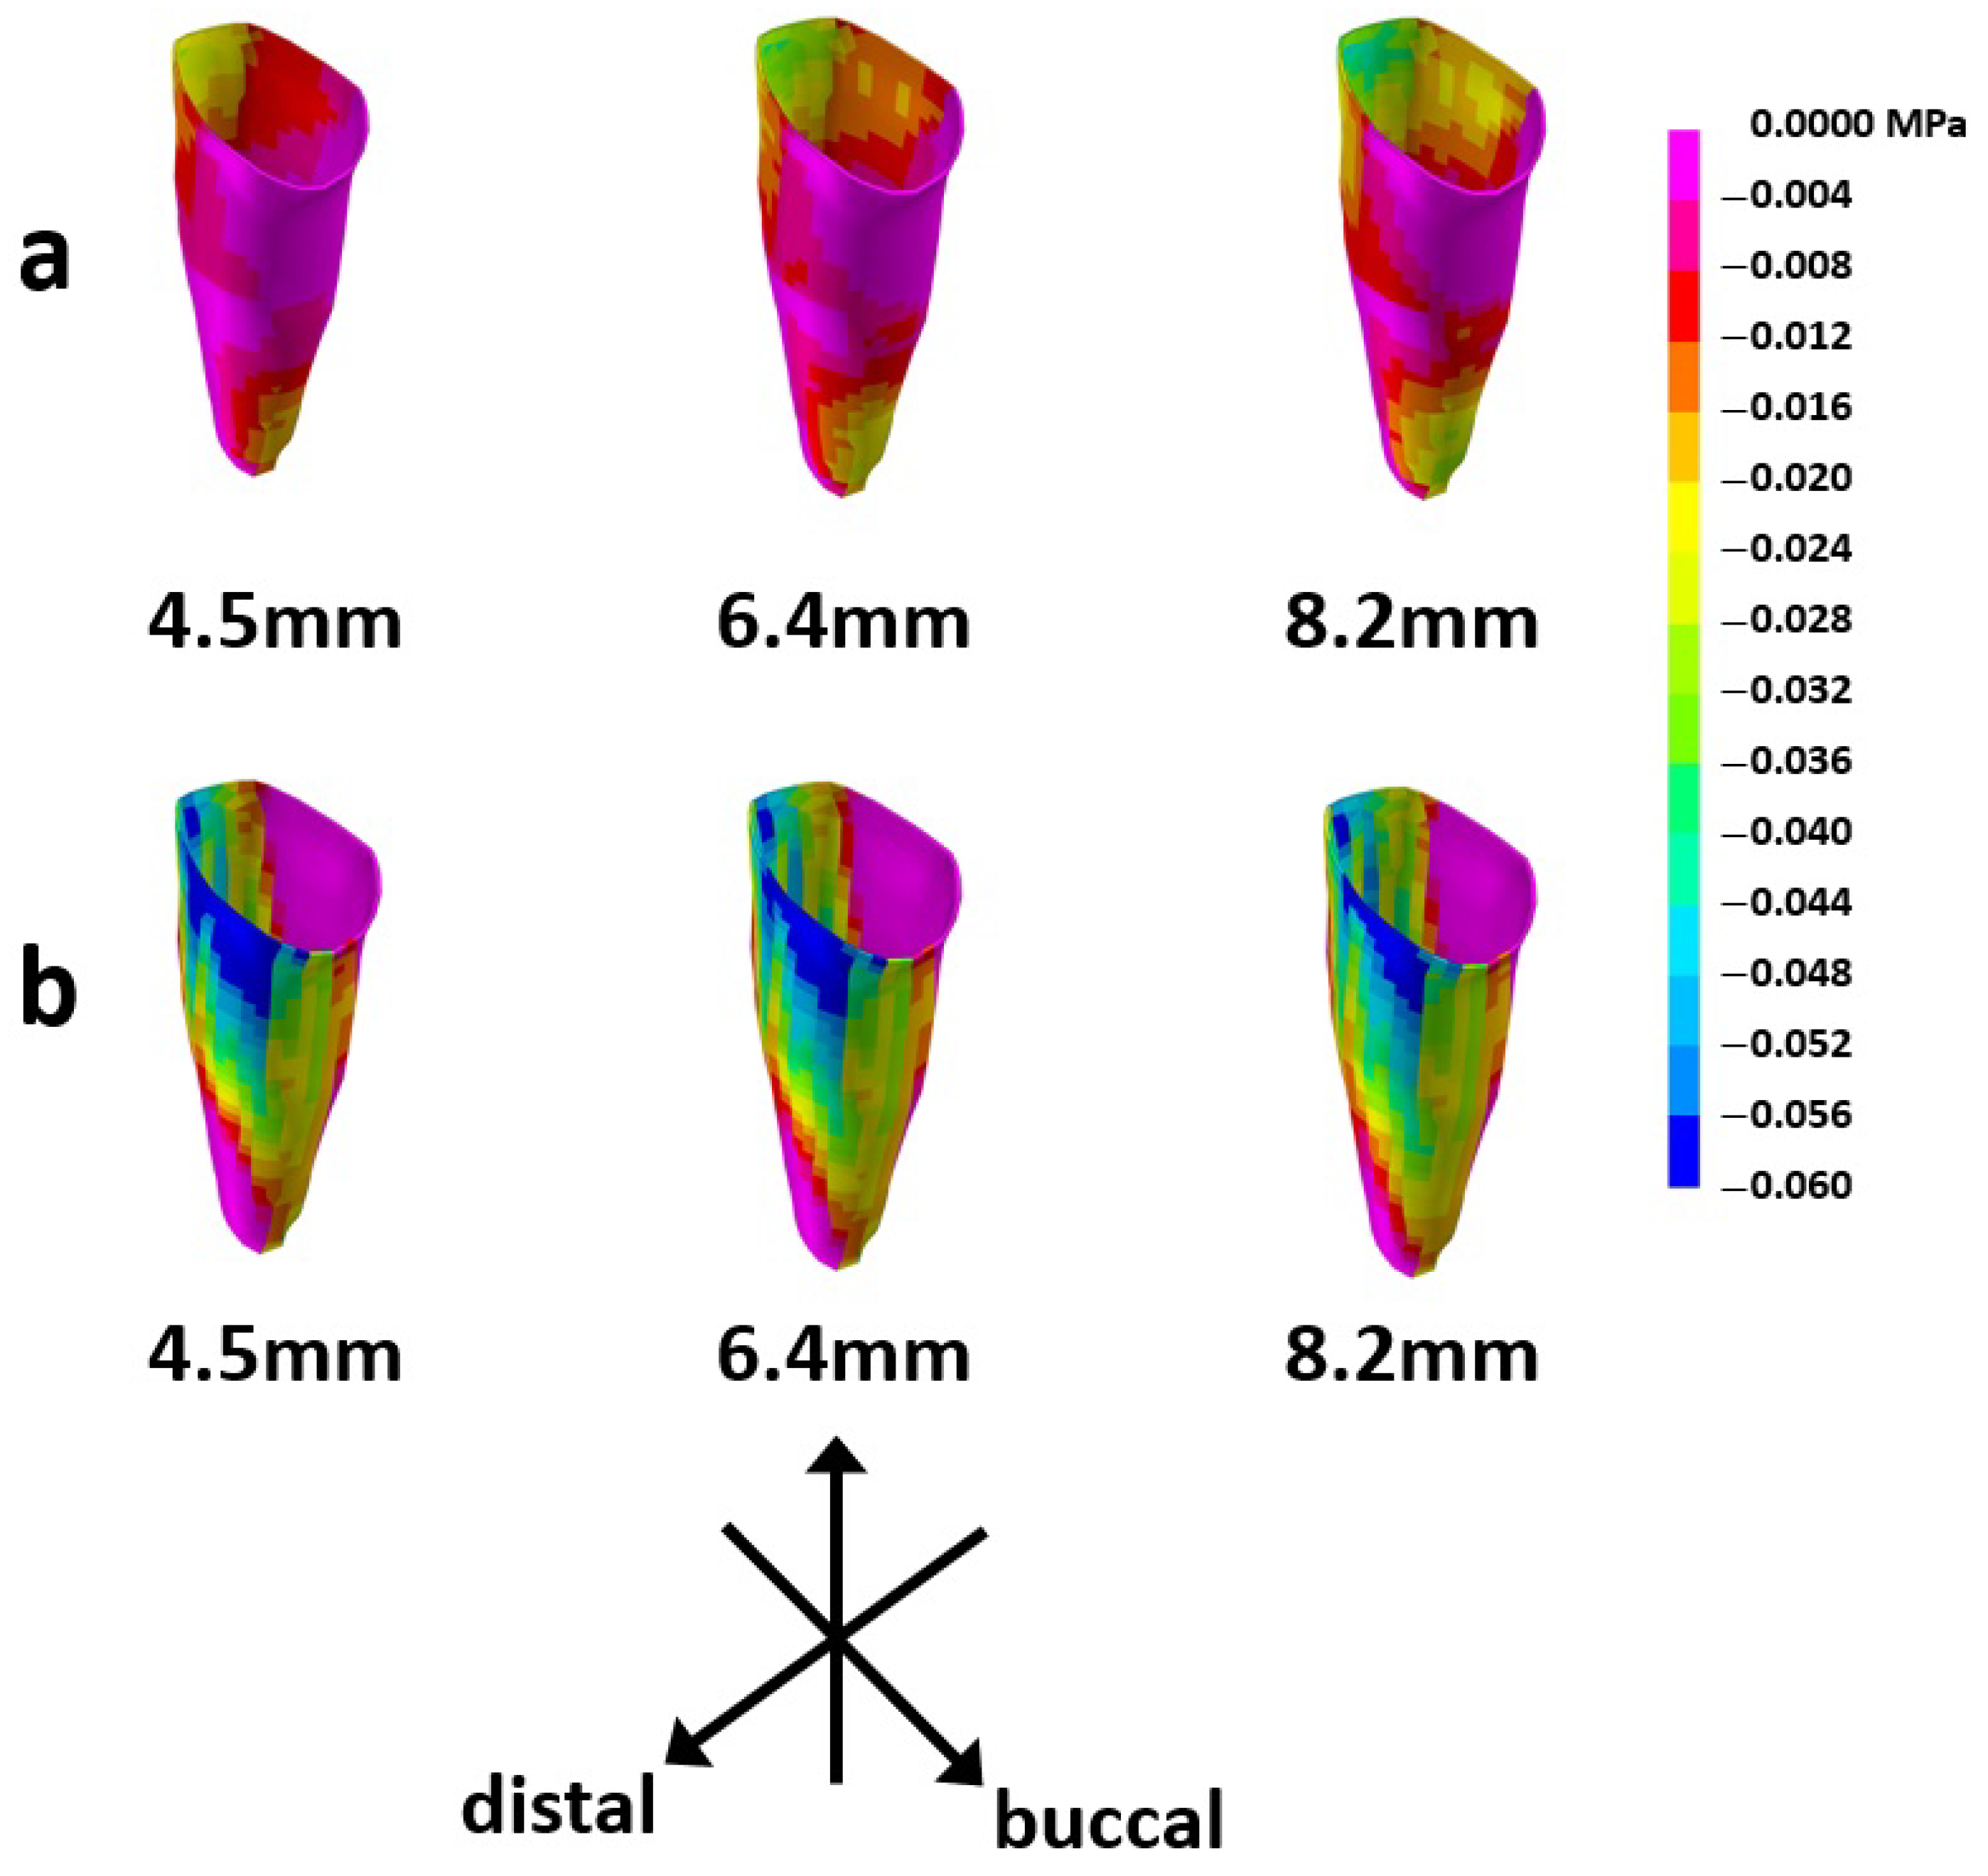

3.4. Compressive Stress Distribution in the PDL

4. Discussion